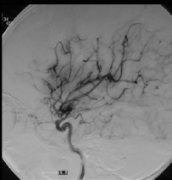

煙霧病圖片(煙霧病手術(shù)過程圖片)

煙霧病手術(shù)過程圖片 煙霧病圖片 3大煙霧病危害 1、短暫性腦缺血發(fā)作 短暫性腦缺血一般由于頸內(nèi)動(dòng)脈末端、大腦前動(dòng)脈、大腦中動(dòng)脈,有時(shí)也包括大腦后...